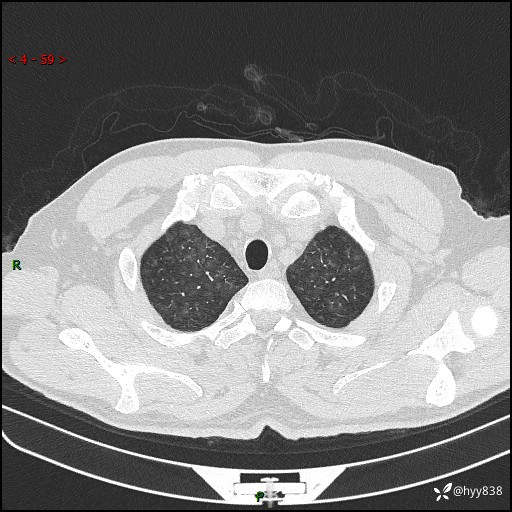

昨天肺结节门诊,“对门”呼吸科申请会诊病例,弥漫性肺部病变---结果公布~

患者年龄:51岁

主诉:发热、咳嗽、咳痰1周

简要病史:患者1周前无明显诱因出现咽喉部疼痛,随后出现咳嗽咳痰,起初干咳为主,后出现咳少许绿色痰,当时有发热,体温为39℃,无畏寒寒战,无胸闷胸痛,无活动后气短,无咯血,无鼻塞流涕,无全身酸痛,患者于诊所输液治疗后体温正常,但仍有咳嗽。患者3天前当地县人民医院就诊,患者仍有咳嗽,咳嗽较为频繁,咳嗽后出现头痛,伴有少许咳痰,随后出现活动后气短,1天前患者再次出现发热,体温最高为40℃,伴有畏寒寒战,伴有乏力、纳差,伴有胸闷不适,无咯血,无全身皮疹,无血尿、尿频尿急尿痛,无腹泻,诊断为“重症肺炎 感染性休克 肾功能异常 痛风”;予以抗感染(亚胺培南),抗病毒(奥司他韦)等对症治疗。患者复查胸部CT提示双肺病灶较前有所增多,建议上级医院就诊,门诊以“肺部感染”收入我科。 起病以来,患者食欲欠佳,大小便正常,睡眠、精神欠佳,体力下降、体重无明显变化。

辅助检查:CT

临床诊断:肺部感染

胸部HRCT